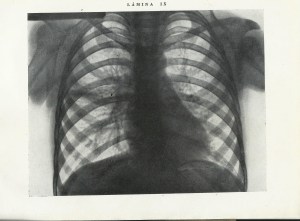

Radiografía de tuberculosis hiliar. Año 1931. Del Atlas de Radiología del Dr. A. Amell Sans

Esquema de la Radiografía de tuberculosis hiliar. Año 1931